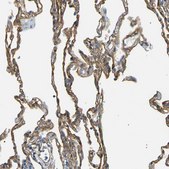

immunohistochemistry: 1:500-1:1000

The Human Protein Atlas project can be subdivided into three efforts: Human Tissue Atlas, Cancer Atlas, and Human Cell Atlas. The antibodies that have been generated in support of the Tissue and Cancer Atlas projects have been tested by immunohistochemistry against hundreds of normal and disease tissues and through the recent efforts of the Human Cell Atlas project, many have been characterized by immunofluorescence to map the human proteome not only at the tissue level but now at the subcellular level. These images and the collection of this vast data set can be viewed on the Human Protein Atlas (HPA) site by clicking on the Image Gallery link. We also provide Prestige Antibodies® protocols and other useful information.

- IHC tissue array of 44 normal human tissues and 20 of the most common cancer type tissues.